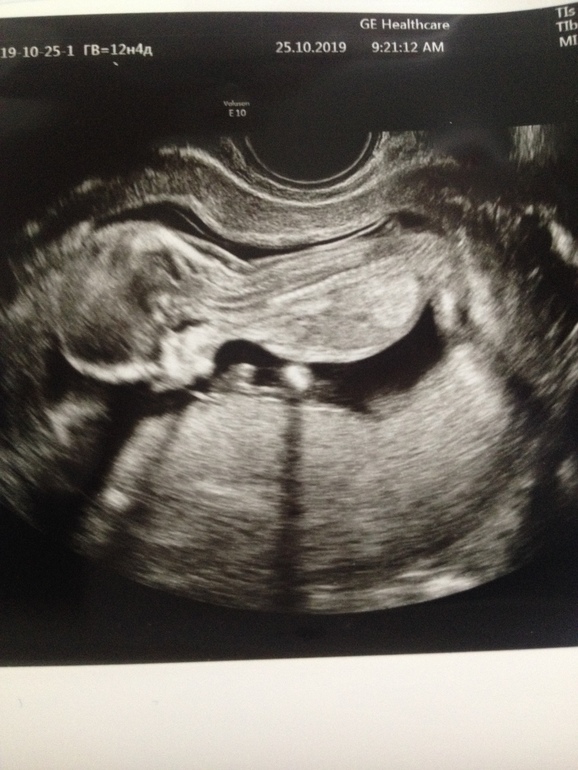

Все у нас замечательно. По календарю 12 недель и 4 дня, а вот по УЗИ поставили 13н и 3д. Когда делала УЗИ в 8 недель, тоже сказали, что опережаем на неделю. Так что либо овуляция была ранняя, либо капитошка торопится расти. Врач УЗИ сказала, что при 3 беременности так может быть и ничего в этом страшного нет. Поторопила с кровью, до среды сказала сдать, там 14 недель стукнет. Платно не хотела идти, дорого. Да и пусть консультация шевелится, раз я у них на учет встала.

Что мы имеем: КТР 72мм, БПР 24мм, ОЖ 70мм, ДБ 11мм. ЧСС 154 удара. длинна шейки 42мм. Все в норме, все посмотрели. По УЗИ никаких патологий. 90% вероятность, что у нас девочка. Что она только не вытворяла, уворачивалась от датчика со скоростью света. В каких только позах мы ее не увидели, и вверх ногами, и вниз, и в танцах. Забавно, конечно.